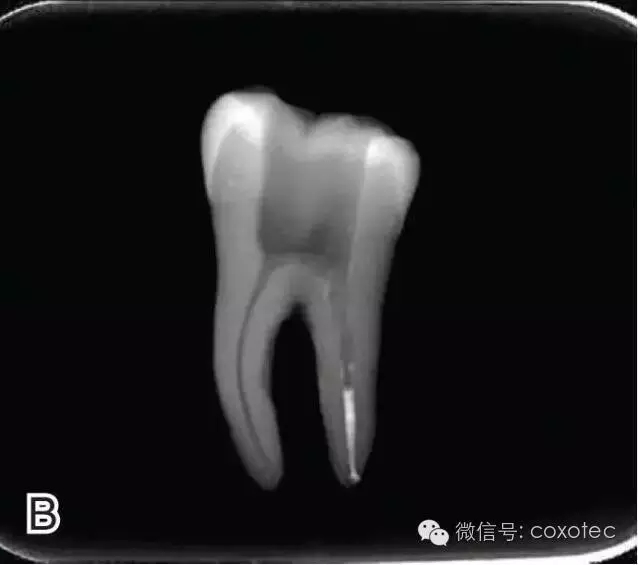

在完成根尖段的充填后,使用熱塑牙膠注射儀對(duì)根管中上段進(jìn)行分層充填,一般分2~3次完成充填,每次充填均使用相應(yīng)直徑大小的垂直加壓器進(jìn)行加壓。拍片確認(rèn)充填效果(圖8)。

I、J.完成根中上段的充填